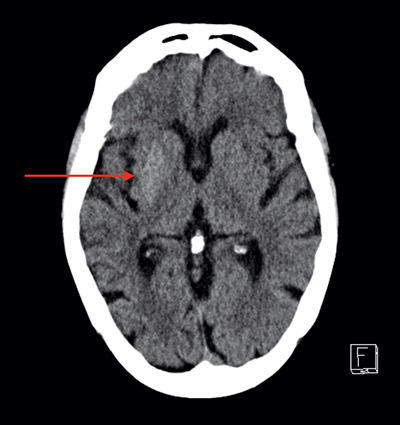

Efterföljande vård gavs under en vecka på medicinavdelning med insulin och vätska på indikationen nyupptäckt typ 2-diabetes. Den sjätte dagen upprepades DT av hjärnan på grund av okoordinerade rörelser i extremiteter på vänster sida. Resultatet visade då oförändrade, eventuellt något mer högattenuerande, fynd i de tidigare beskrivna områdena (Figur 2). Koordinationsstörningarna var dock inte särskilt uttalade, och patienten skrevs därför ut till hemmet med uppföljning endast av sin nyupptäckta diabetes.

Figur 2. DT av hjärnan hos patienten i fallbeskrivningen dag 6 efter inläggning för hyperglykemi visar något mer högattenuerande fynd i basala ganglier på höger sida. Patienten hade vid tillfället börjat visa symtom på vänstersidiga ofrivilliga rörelser.